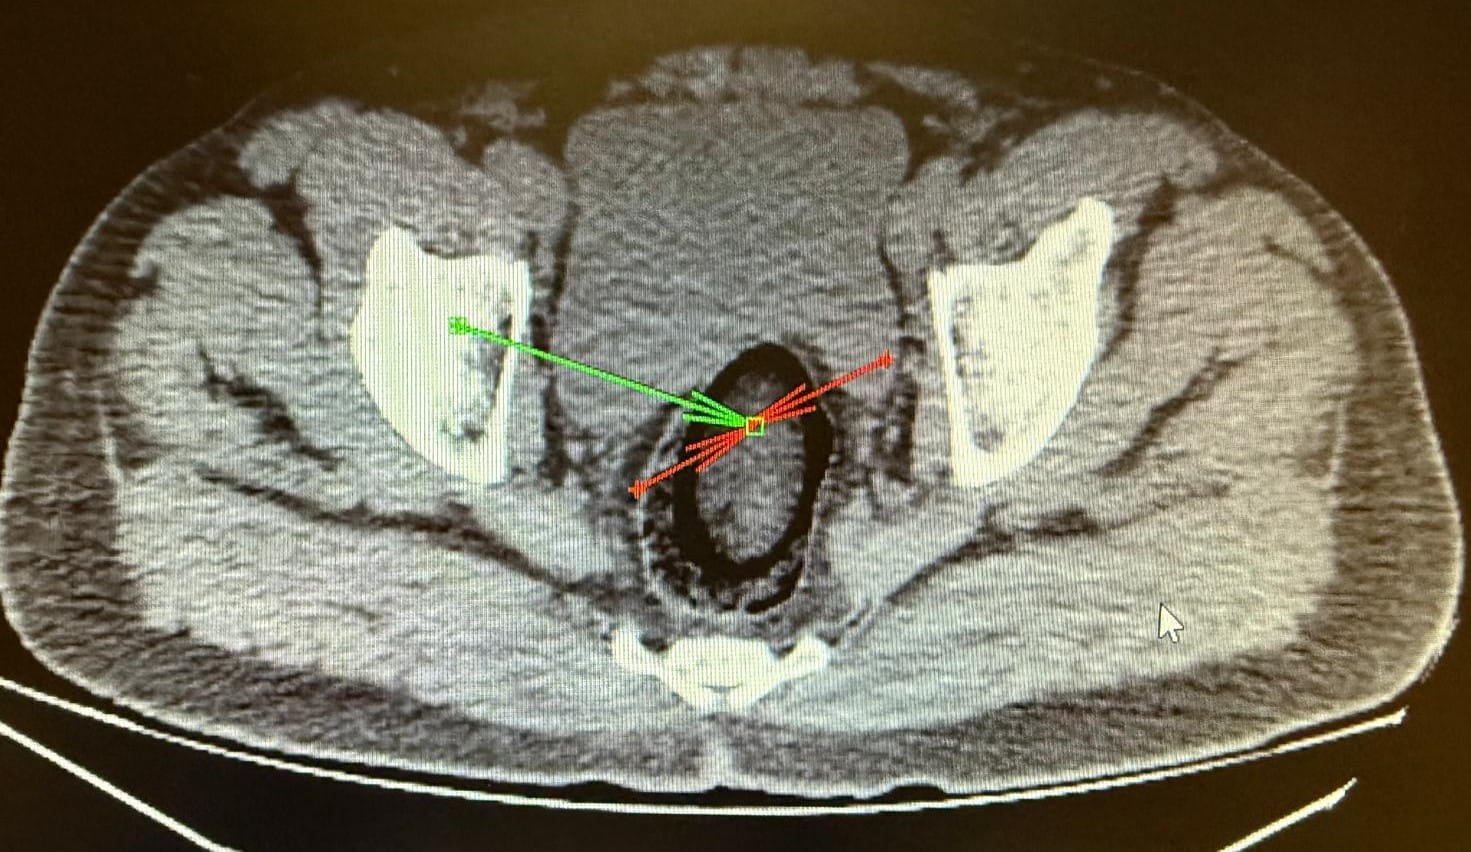

Kars Harakani Devlet Hastanesi'ne götürülen F.H.'nin çekilen röntgeninde, makatında uyuşturucu tespit edildi. İranlı yolcunun makatına zulaladığı 105,98 gram metamfetamin, cerrahi operasyonla çıkarıldı.